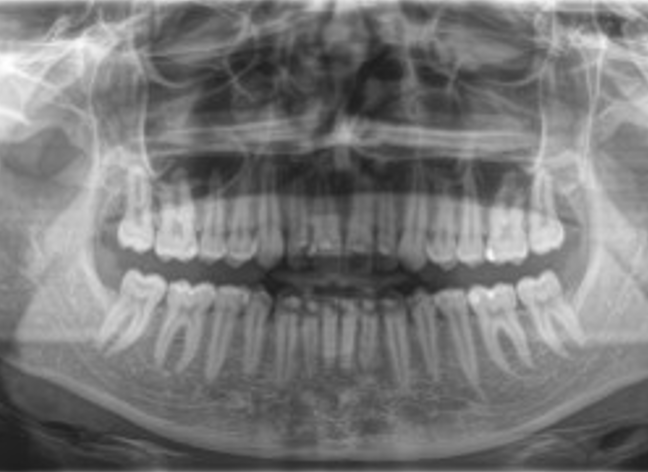

Ортопантомограма (ОПТГ) потрібен щоб:

• Оцінити стан зубів, коріння, каналів. А також побачити пломби, імпланти, коронки, проаналізувати структуру тканин пародонту.

• Виявити приховані запальні процеси, каріозні порожнини, патологічні утворення (кісту, абсцес).

• Виявити пародонтальні кишені.

• Провести оцінку стану навколозубних тканин, верхньощелепних синусів, скронево-щелепного суглоба.

• Визначити параметри щелепної кістки, положення, стан зубів у ряду, включаючи зуби мудрості.

• Хоча панорамний знімок — один з основних діагностичних інструментів стоматолога, він має деякі похибки:

• Геометричні спотворення, що не дають 100% точність зображення (корекція змін становить 20%).

• Навіть мінімальне зміщення щелепи обумовлює зміщення фокусної плями, через що зображення стає стисненим або розтягнутим.

• Через структурні відмінності у тканинах, що потрапили в зону дії рентгенівського випромінювання, щільні тканини не дають достовірно оцінити стан менш щільної губчастої кістки.

• Двовимірний знімок щелепи зубів не оцінює форму кісткового гребеня, структуру кістки на рівні, що цікавиться.

Ортопантомограма — це швидше допоміжний діагностичний інструмент, що надає оглядову картину і виявляє явну патологію. На відміну від панорамного знімка, 3D комп’ютерна томографія дає не одне плоске зображення щелепи. Лікар отримує низку послідовних зображень у різній проекції без спотворень, властивих панорамного знімка. Отримане тривимірне зображення дозволяє лікарю розглянути щелепно-лицьову зону на будь-якій глибині з усіх боків та кутів. Приклад: на панорамному знімку видно правильний імплант, а на КТ дослідженні виявлені помилки при встановленні.